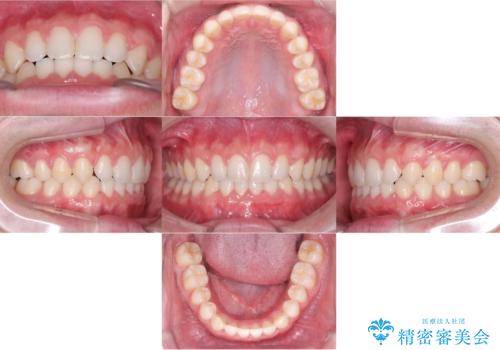

前歯のねじれ・ガタガタを10か月で改善!20代女性の矯正治療|クリアブラケットでむし歯になりにくい歯並びへ改善

担当医 齋藤佑磨

前歯のねじれ 矯正治療による歯並び改善

担当医 大元洋佑